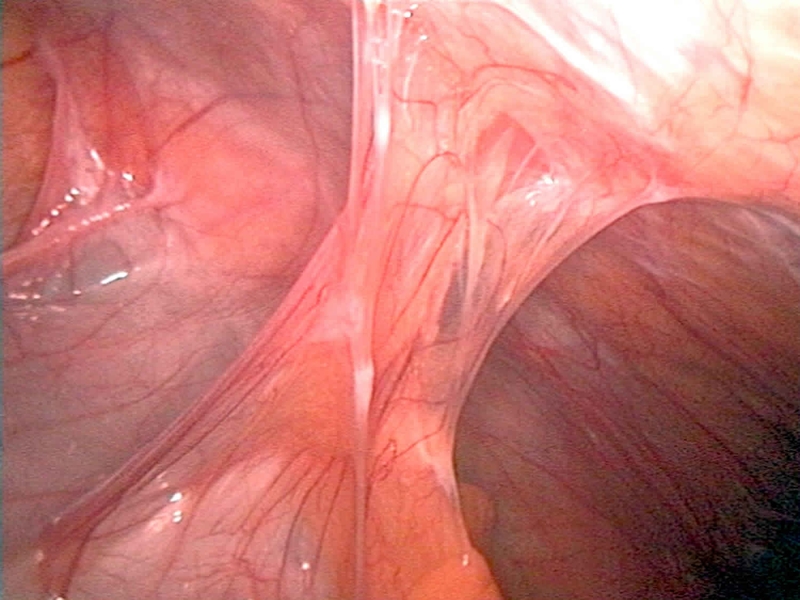

Phẫu thuật áp dụng trong tách dính buồng tử cung là phẫu thuật nội soi. Kỹ thuật này dùng một ống soi nhỏ có gắn nguồn sáng và camera đưa vào tử cung qua đường âm đạo. Hình ảnh bên trong buồng tử cung sẽ được truyền về màn hình. Từ đó giúp bác sĩ quan sát cấu trúc bên trong buồng tử cung và tiến hành tách dính.

Các bác sĩ sẽ bóc tách thành tử cung trước và sau bị dính một phần hay toàn phần. Sau đó, một dụng cụ sẽ được đặt vào giữa hai thành tử cung để ngăn chúng dính trở lại. Sau tách dính, các bác sĩ cũng sẽ chỉ định bệnh nhân dùng thuốc để kích thích lớp nội mạc tử cung phát triển dày hơn.